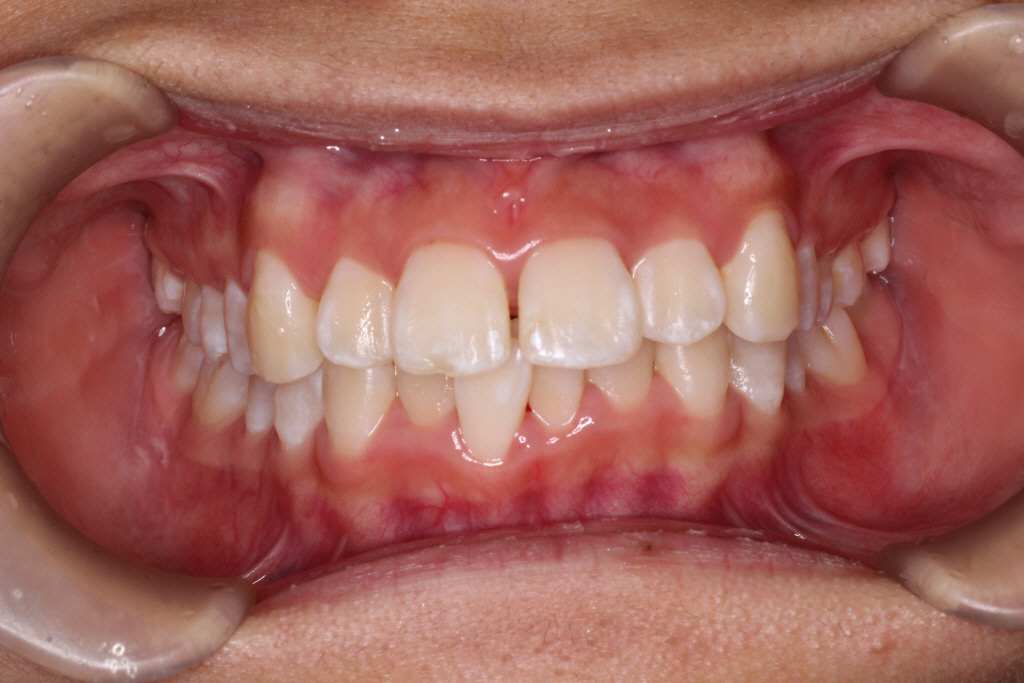

初診時の写真です。

前歯にはがたつき(叢生)がみられ、奥歯は上の歯と下の歯が1歯対1歯で噛んでいることがわかります。

つまり出っ歯の噛み合わせです。

診断:上顎前突・前歯部叢生